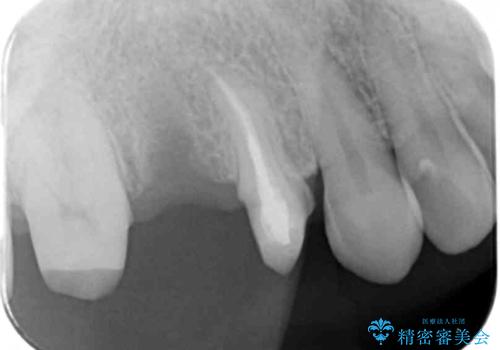

- 他院でブリッジの仮歯を入れたが、外れやすいため転院を希望された患者様です。

支台歯の形が角度が大きくついた形に形成してあり、外れやすい形になっていたため修正してから歯型をとりました。